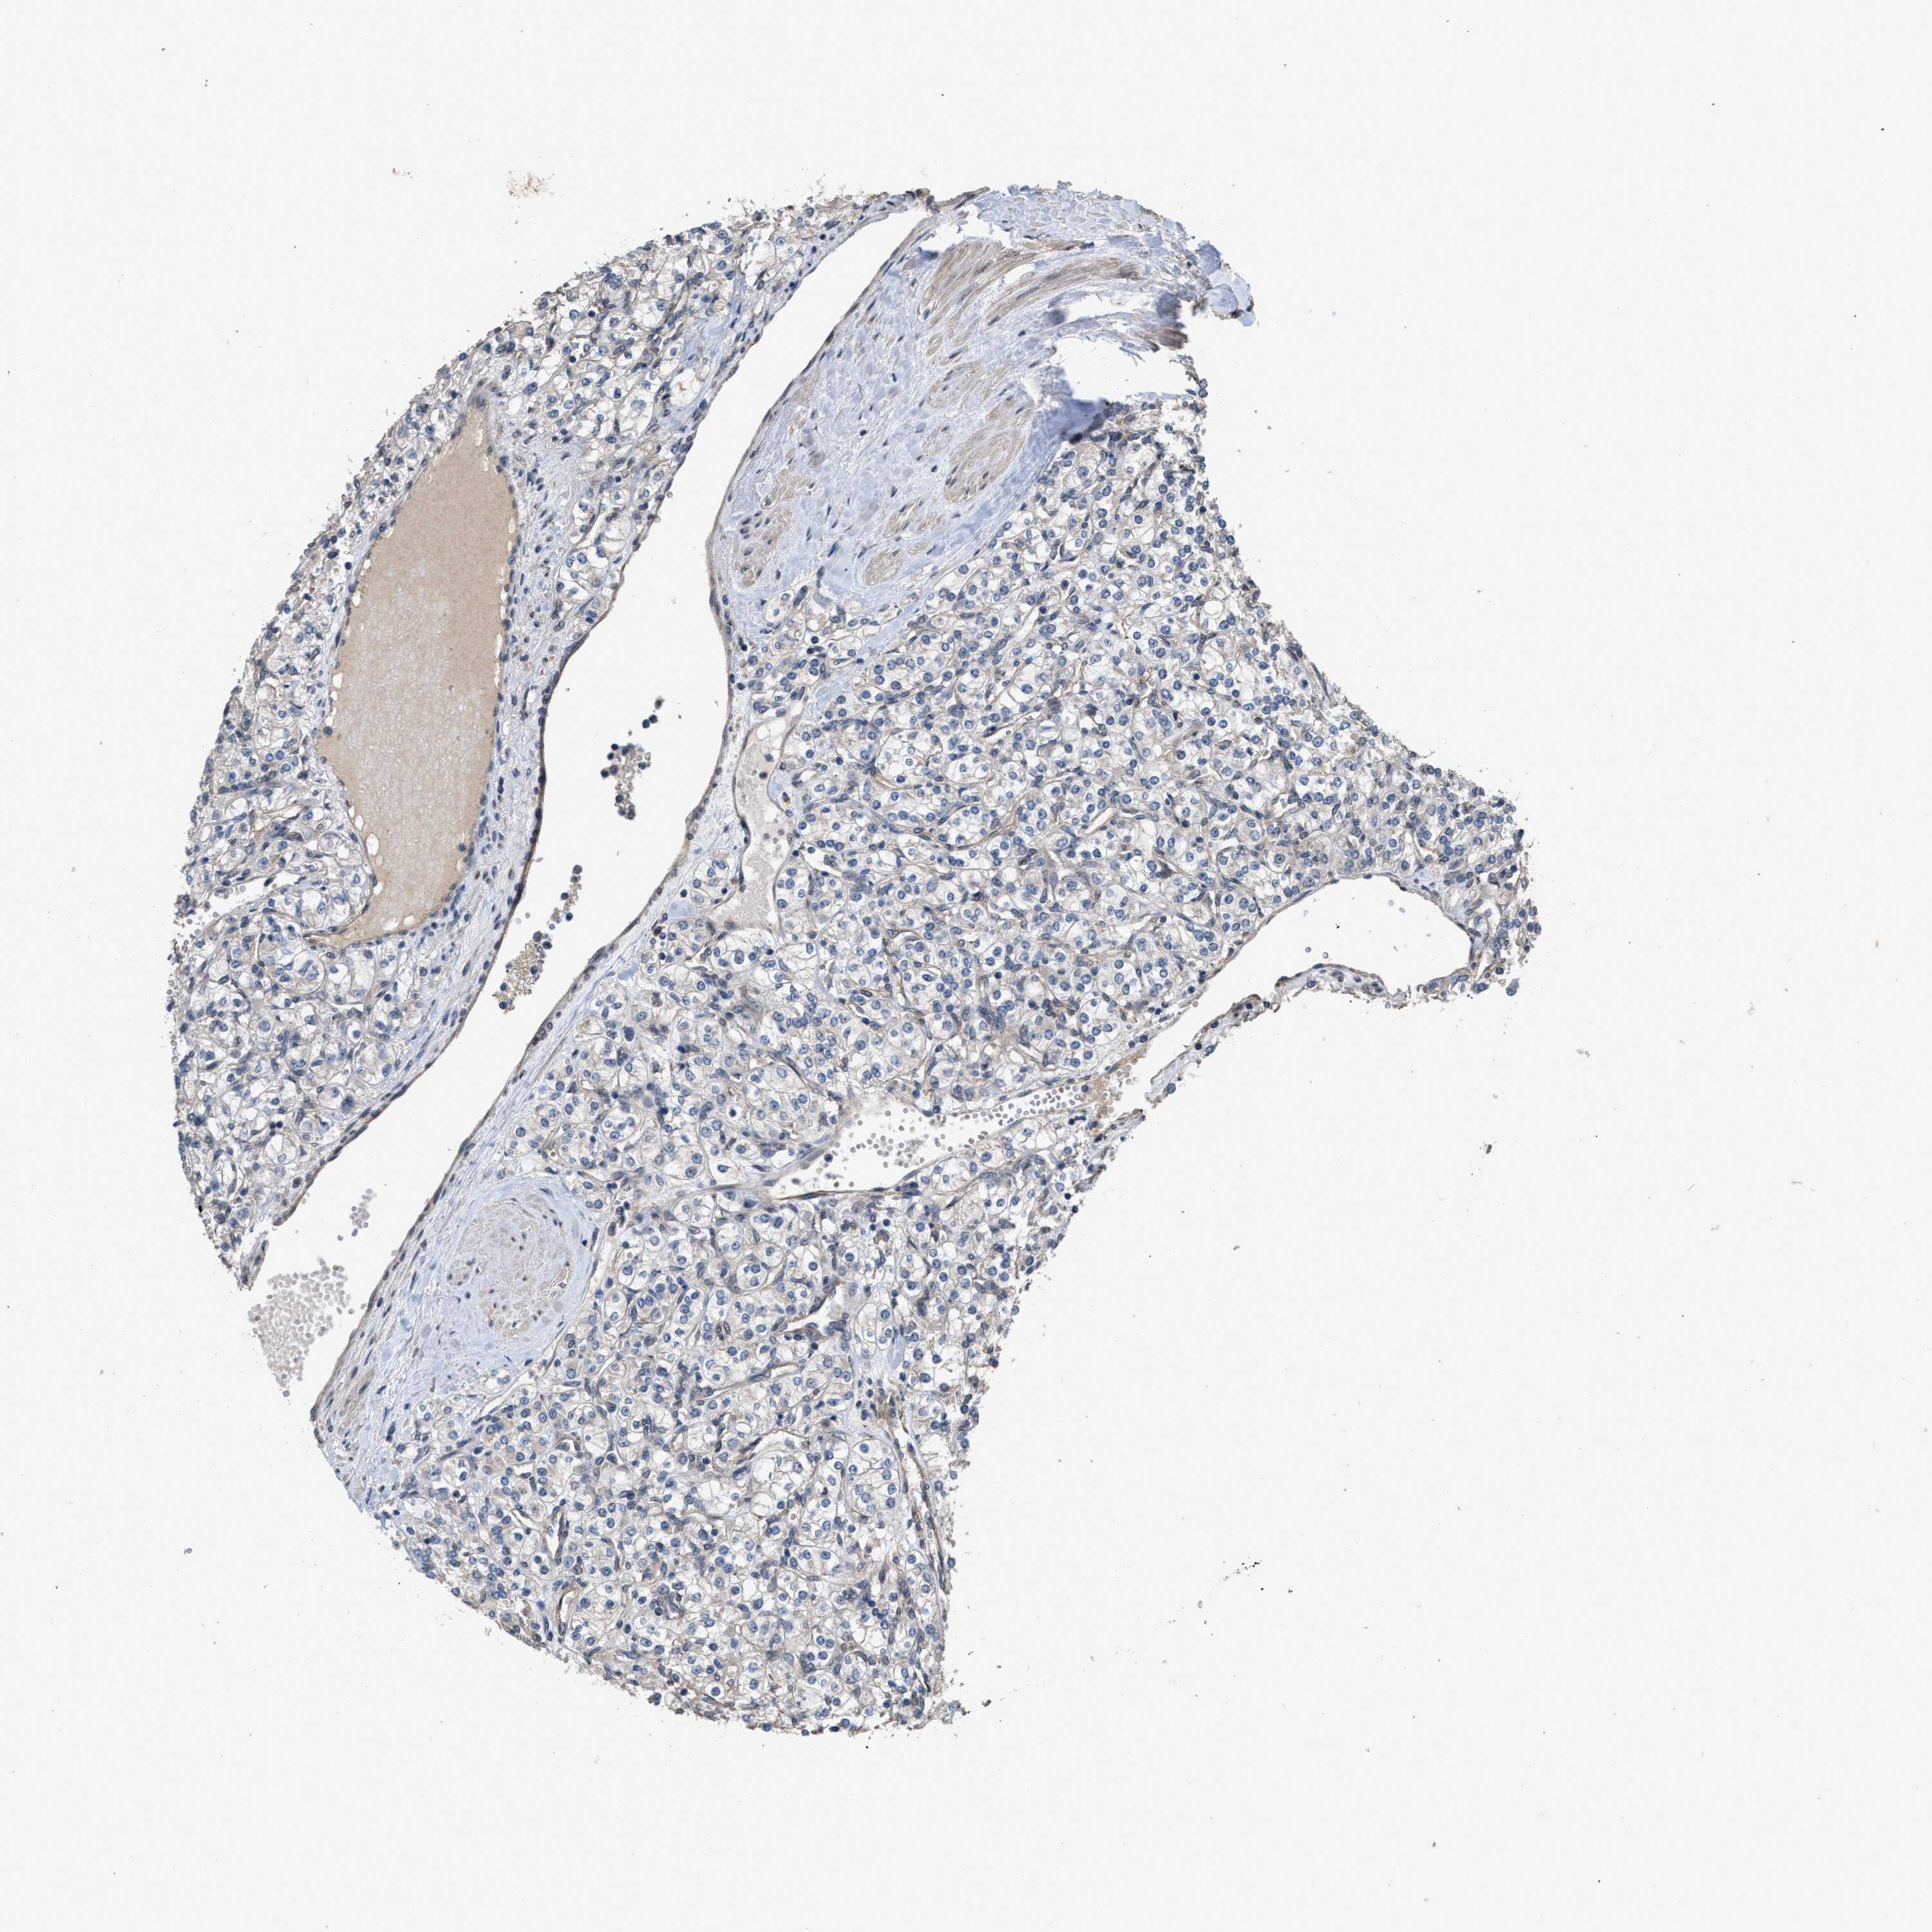

KIDNEY RENAL CLEAR CELL CARCINOMA (TCGA) - Interactive survival scatter ploti

The Survival Scatter plot shows the clinical status (i.e. dead or alive) for all individuals in the patient cohort, based on the same data that underlies the corresponding Kaplan-Meier plots. Patients that are alive at last time for follow-up are shown in blue and patients who have died during the study are shown in red.

The x-axis shows the expression levels (FPKM) of the investigated gene in the tumor tissue at the time of diagnosis. The y-axis shows the follow-up time after diagnosis (years). Both axes are complimented with kernel density curves demonstrating the data density over the axes. The top density plot shows the expression levels (FPKM) distribution among dead (red) and alive patients (blue). The right density plot shows the data density of the survived years of dead patients with high and low expression levels respectively, stratified using the cutoff indicated by the vertical dashed line through the Survival Scatter plot. This cutoff is automatically defined based on the FPKM cutoff that minimizes the p-score. The cutoff can be changed by dragging the vertical line or by entering a cutoff value in the square labeled "Current cut-off".

Under the Survival Scatter plot the p-score landscape (black curve; left axis) is shown together with dead median separation (red curve; right axis). Dead median separation is the difference in median mRNA expression between patients who have died with high and low expression, respectively. It is calculated as follows: median FPKM expression of dead patients with high expression - median FPKM expression of dead patients with low expression. This is intended to aid the user in visually exploring custom cutoffs and the associated p-scores and dead median separation.

Individual patient data is displayed and can be filtered by clicking on one or more of the category buttons on the top of the page. Categories describing expression level and patient information include: high, low, alive, dead, female, male and tumor stages. The scale of the x-axis can be toggled between linear and log-scale by clicking on the "x log" button. Mouse-over function shows TCGA ID, patient information and mRNA expression (FPKM) for each patient.

& Survival analysisi

Kaplan-Meier plots summarize results from analysis of correlation between mRNA expression level and patient survival. Patients were divided based on level of expression into one of the two groups "low" (under cut off) or "high" (over cut off). X-axis shows time for survival (years) and y-axis shows the probability of survival, where 1.0 corresponds to 100 percent.

UTRN is validated prognostic, high expression is favorable in Kidney Renal Clear Cell Carcinoma (TCGA)

Best expression cut offi

Based on the FPKM value of each gene, patients were classified into two groups and association between prognosis (survival) and gene expression (FPKM) was examined. The best expression cut-off refers the FPKM value that yields maximal difference with regard to survival between the two groups at the lowest log-rank P-value. Best expression cut-off was selected based on survival analysis .

When clicking on this number, the vertical dashed line indicating cut-off, the interactive survival plot, and the Kaplan-Meier curve will be adjusted to show results based on the best expression cut-off.

: 38.77

Median expressioni

Median expression refers to the median FPKM value calculated based on the gene expression (FPKM) data from all patients in this dataset. When clicking on this number, the vertical dashed line indicating cut-off, the interactive survival plot, and the Kaplan-Meier curve will be adjusted to show results based on the median expression.

: N/A

Median follow up timei

Median follow up time refers to the median time (years) after diagnosis with this type of cancer, based on clinical data from all patients in this dataset.

P scorei

Log-rank P value for Kaplan-Meier plot showing results from analysis of correlation between mRNA expression level and patient survival.

N/A

5-year survival highi

5-year survival for patients with higher expression than the expression cutoff.

For melanoma and glioma, 3-year survival is shown.

5-year survival lowi

5-year survival for patients with lower expression than the expression cutoff.

Average pTPM 40.8

Number of samples 521